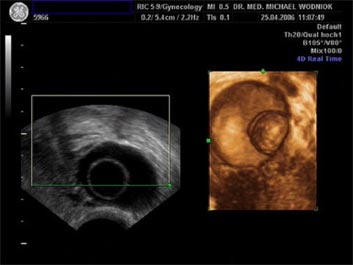

Hochauflösende Ultraschalluntersuchungen in Kombination mit der 3D-4D Technik werden in unserer Praxis routinemäßig durchgeführt. Dabei werden im Rahmen der Vorsorgeuntersuchung, sowie bei reinen vorsorglichen Ultraschalluntersuchungen auf Wunsch, auffällige Tastbefunde und noch unentdeckte Befunde weiter sonografisch abgeklärt. Bei zweifelhaften Befunden der Brüstdrüsen oder von Organen der inneren Genitalien kann der zusätzliche Einsatz der Farbdopplertechnik sehr hilfreich sein. Dabei stellt diese Technik bildlich sehr genau den Blutfluss, die Flussgeschwindigkeit, den Blutflusswiderstand sowie die Blutflussrichtung aller Blutgefässe dar. Die Interpretation dieser Ergebnisse fließt als zusätzlicher „Marker“ in die Entscheidung für das weitere klinische Vorgehen ein. Ein zunächst als völlig unauffällig eingestufter Ultraschallbefund eines zystischen Befundes im Eierstock wird bei einem unerwartet auffälligen Blutfluss an der inneren Zystenwand eine zeitnahe weitere Abklärung zu Folge haben. ![]() ![]() ![]()